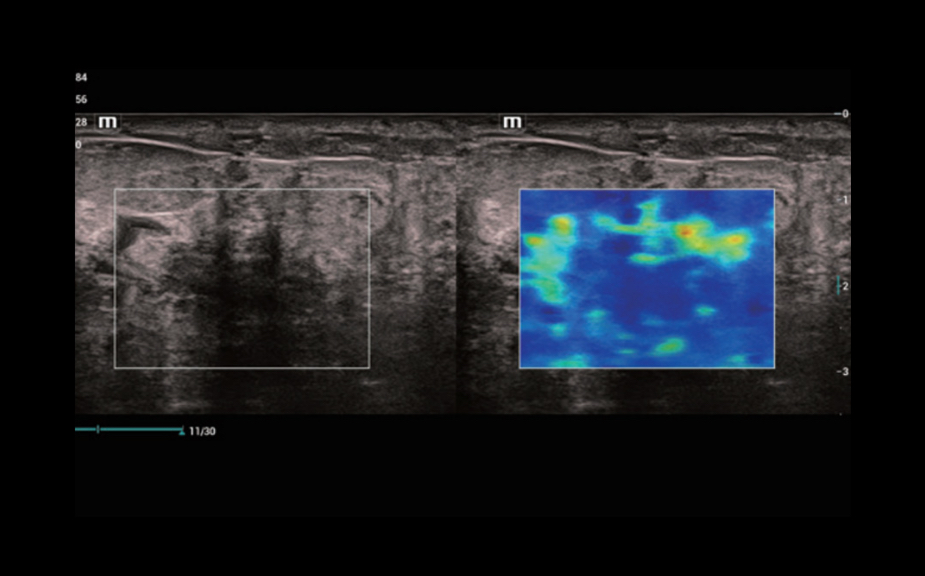

Инновационная оценка жесткости: HiFR STE

В 10 раз более высокая частота кадров при работе режима STE

Высокая чувствительность к движению для повышения стабильности и точности

HiFR STE новообразования молочной железы

Инновационная оценка жесткости: HiFR STE

В 10 раз более высокая частота кадров при работе режима STE

Высокая чувствительность к движению для повышения стабильности и точности

HiFR STE новообразования молочной железы